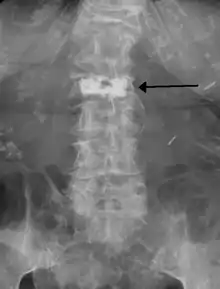

During the procedure, bone cement is injected with a biopsy needle into the collapsed or fractured vertebra. The needle is placed with fluoroscopic x-ray guidance. The cement (most commonly poly methyl methacrylate (PMMA), although more modern cements are used as well) quickly hardens and forms a support structure within the vertebra that provide stabilization and strength. The needle makes a small puncture in the patient's skin that is easily covered with a small bandage after the procedure.[20]